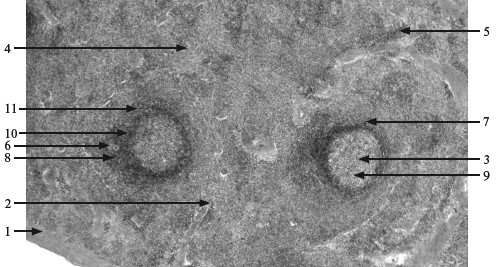

Рис. 12.3. Селезенка. х 130.

1 – капсула; 2 – трабекула; 3 – белая пульпа; 4 – красная пульпа; 5 – селезеночные тяжи; 6 – артерия узелка; 7 – лимфоидный узелок; 8 – периартериальная зона; 9 – центр размножения; 10 – мантийная зона; 11 – маргинальная зона.